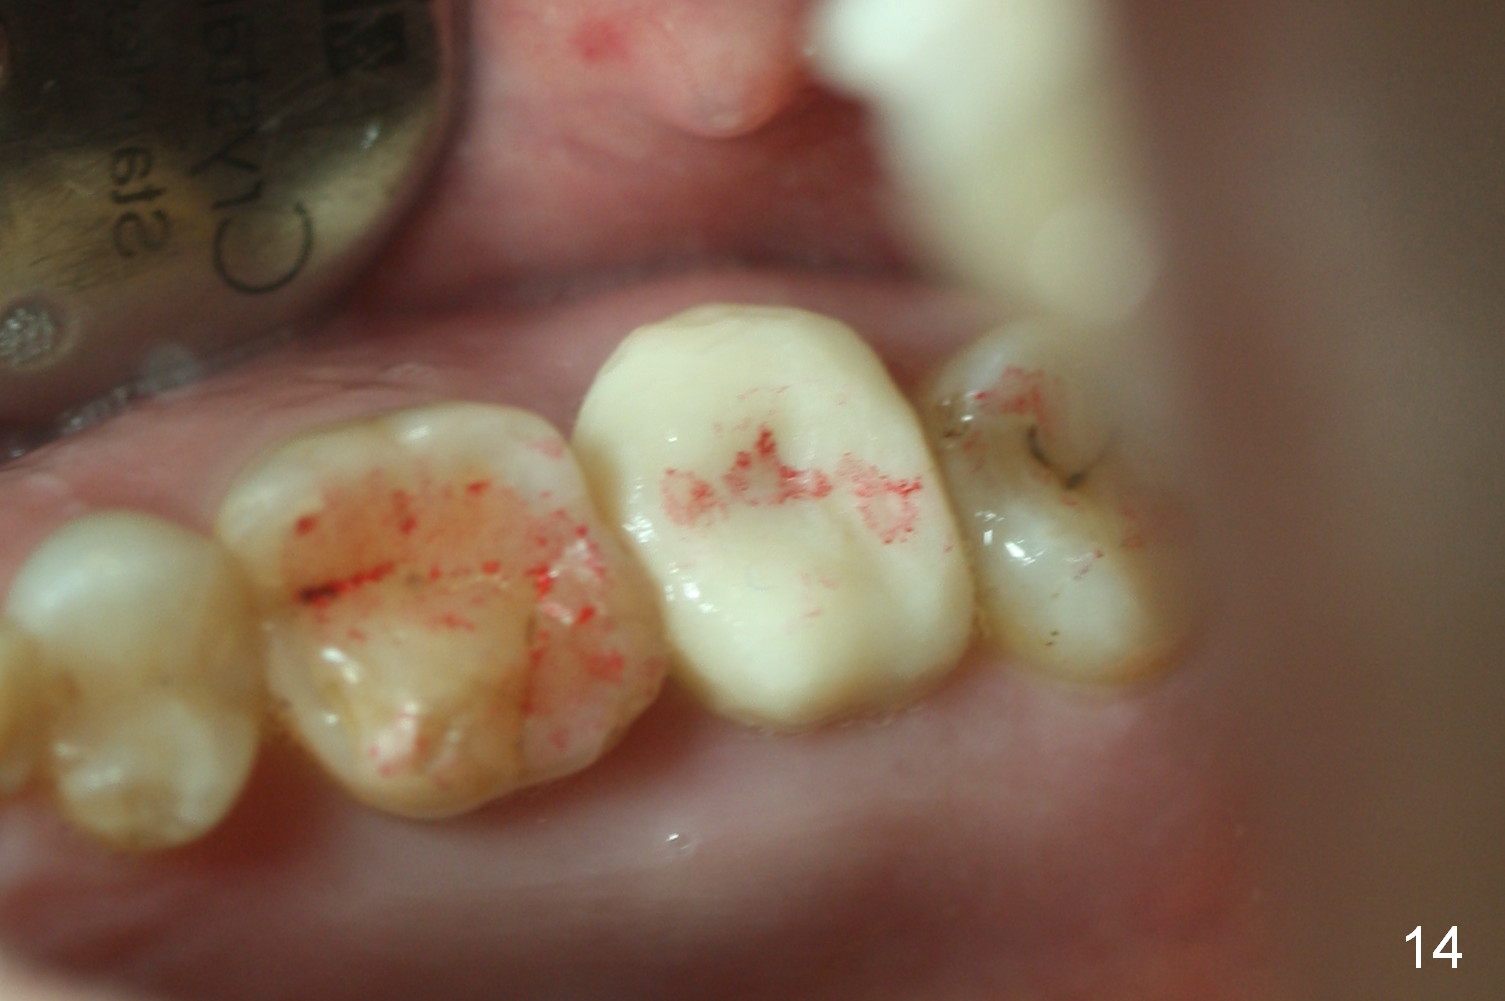

The patient returns because of provisional dislodgement 4 days postop. It appears that the socket shrinks (Fig.13 mirror view) with partial resolution of collagen dressing (*, as compared to Fig.10). The provisional is relined and reseated with occlusion checked (Fig.14). There is no sign or symptom of infection. The patient is pleased.